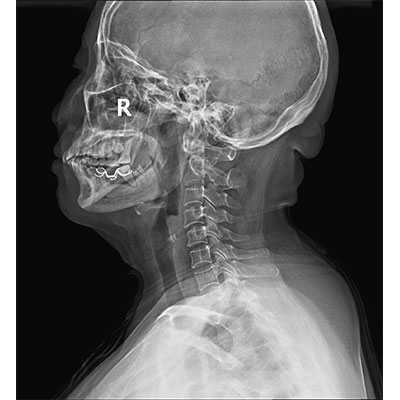

● 采用自主研發(fā)的技術,在保證優(yōu)質圖像的前提下,大大降低X射線劑量,用心呵護醫(yī)護工作者及患者的健康。

● 短曝光時間,便于老年人、兒童、殘疾人進行臨床拍攝。避免這類群體因不能有效控制身體運動等因素造成的運動偽影,提高攝片質量及效率。